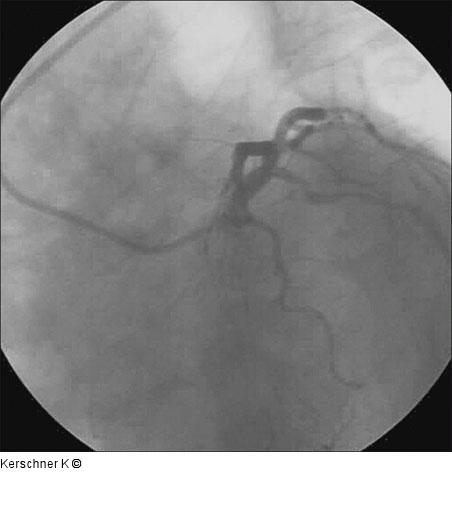

Abbildung 15: Kontrollangiographie Kontrollangiographie nach 3 Monaten - LAO/kaudal. |

Kontrollangiographie nach 3 Monaten - LAO/kaudal. |